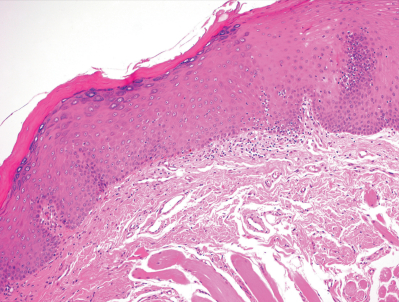

72歳の男性。歯科医院で右側舌縁部の白斑を指摘され、紹介により来院した。2年前に気付いたが疼痛はなく、性状も大きさも変化はないという。初診時の口腔内写真と生検時のH-E染色病理組織像を別に示す。

考えられる対応はどれか。2つ選べ。